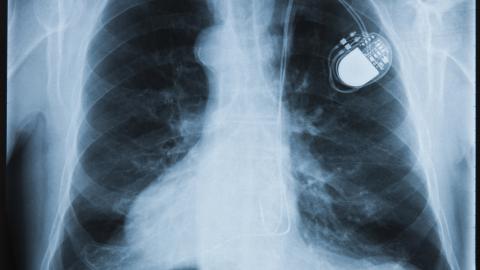

Cardiac implantable electronic devices

Pacemakers

Implantable Cardioverter Defibrillators (ICDs)

Cardiac resynchronization therapy (CRT) device

Loop recorders